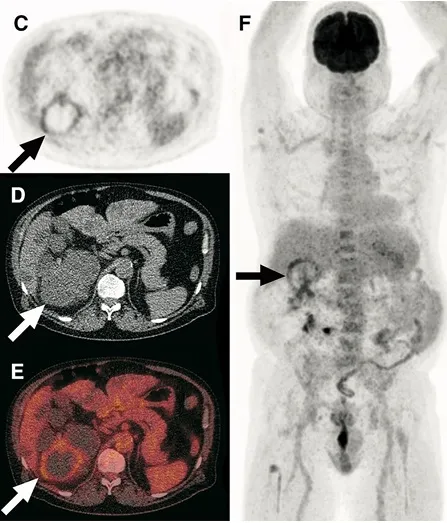

Doação renal em mulheres jovens pode impactar mais o feto do que a mãe — e esse dado muda o pré-operatório. O maior estudo já feito mostra aumento de PIG e sinais de disfunção placentária silenciosa, especialmente em nulíparas. Se você ainda não discute isso de forma explícita no consentimento, talvez esteja subestimando o risco.